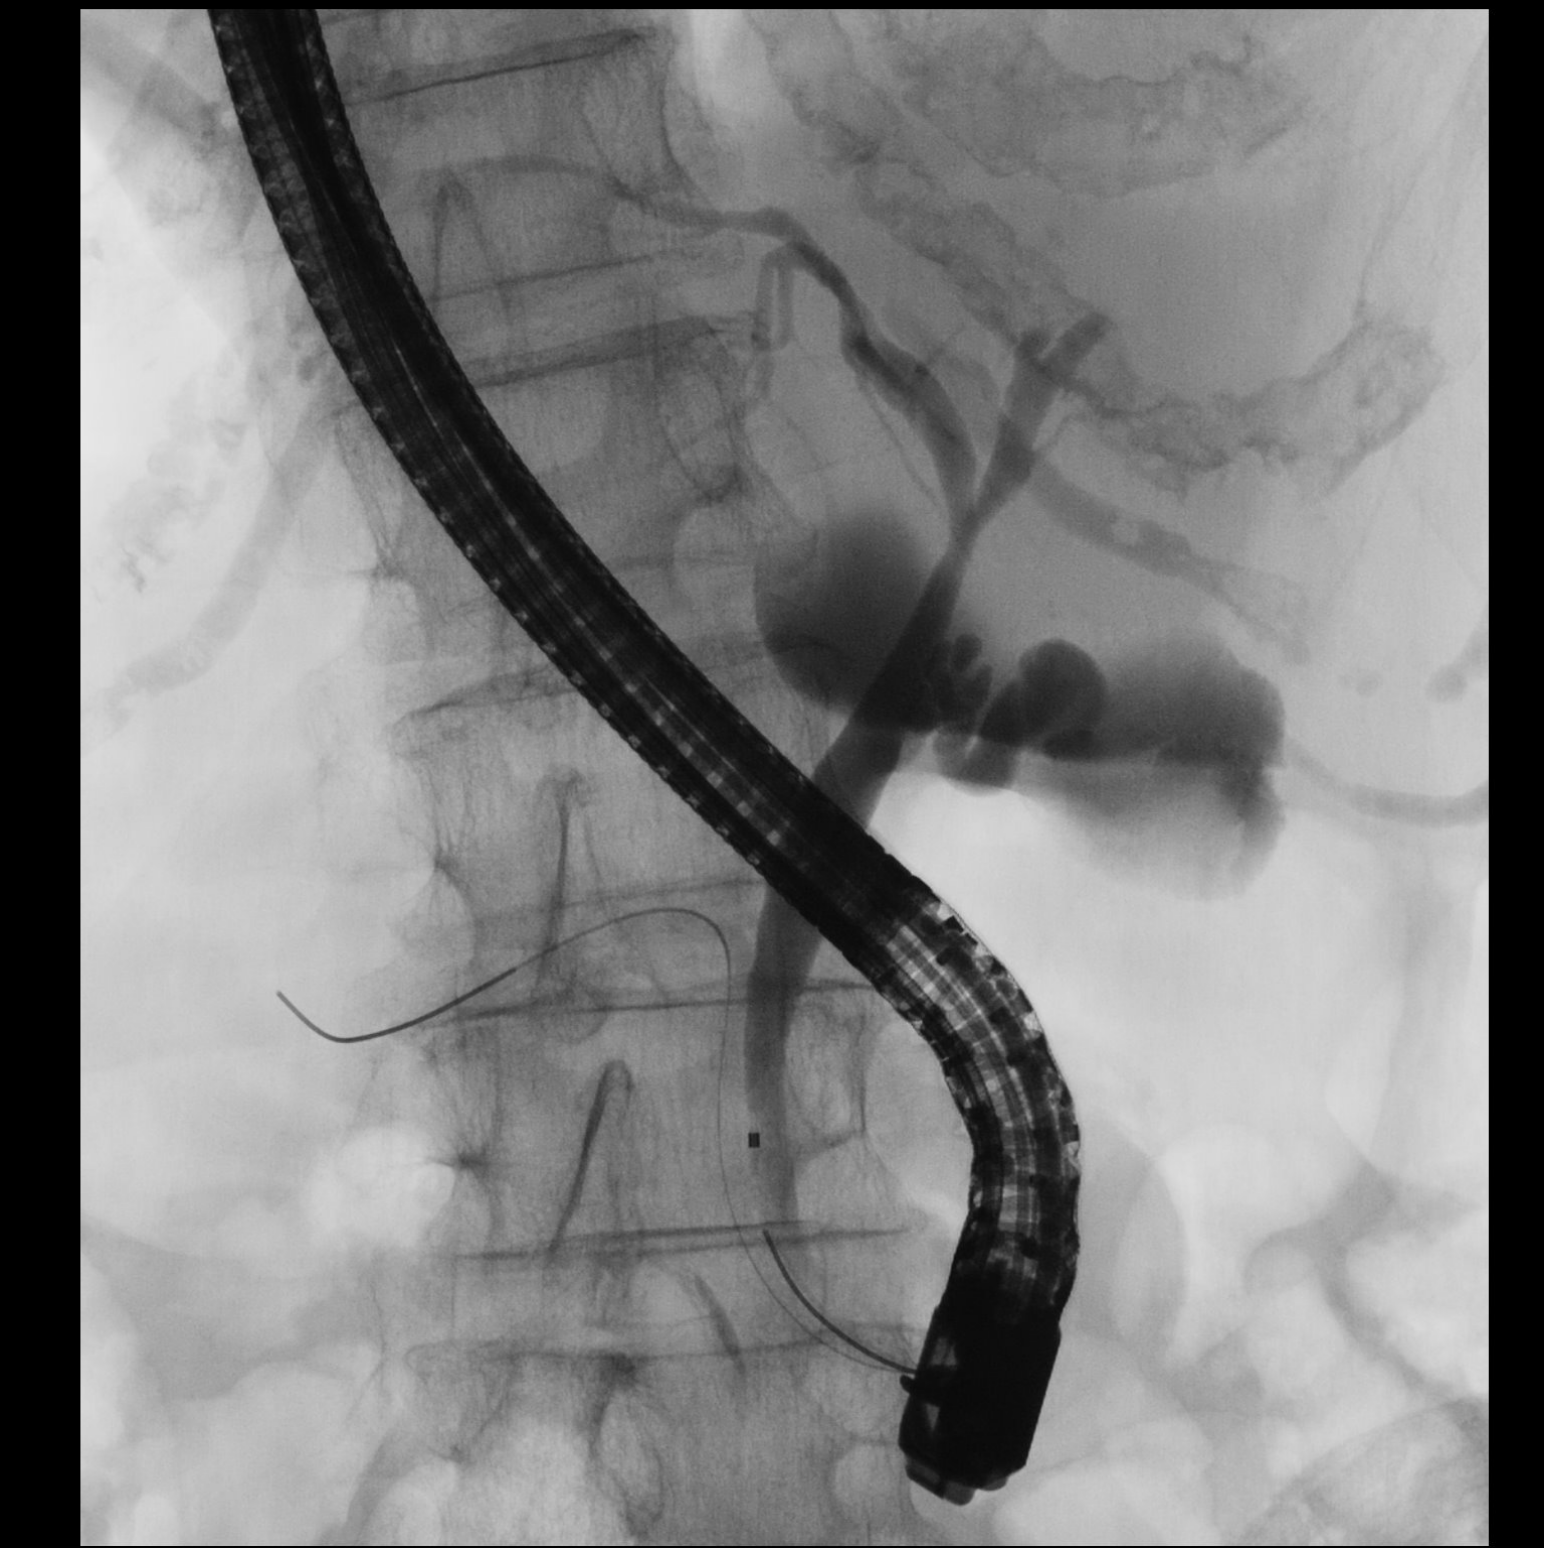

内視鏡的逆行性胆管膵管造影(ERCP)は、胆管や膵管の病気を詳しく調べるための検査です。内視鏡を口から挿入し、造影剤を注入して胆管や膵管をレントゲン撮影します。

ビデオスコープを口から十二指腸まで挿入したうえで、先端から出したカテーテルを胆管・膵管に挿入し造影剤を注入してレントゲン撮影を行います。形態を観察し異常が疑われた場合には、細胞を採取して病気の診断を行います。

ERCPは、胆管癌の診断や閉塞性黄疸の治療(内視鏡的胆道ドレナージ)、早期膵癌の診断等に有用な検査です。